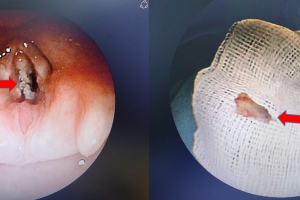

Trẻ chấn thương vỡ khí quản hiếm gặp – Vừa qua bệnh viện Nhi Đồng Thành Phố tiếp nhận một trường hợp trẻ N. V. T. Ph. 12 tháng tuổi, nam, ngụ ở Hậu Giang...